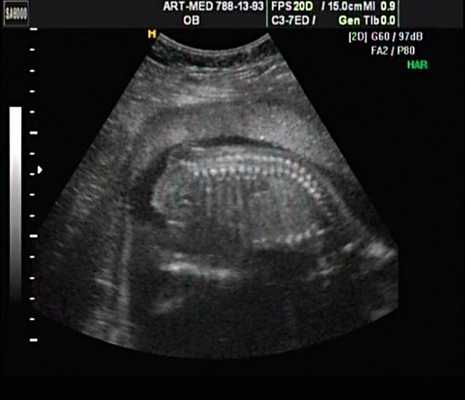

Нагрузка сопротивлением возникает при ситуации, когда выброс крови из желудочков сердца в магистральные сосуды затруднен на уровне полулунных клапанов (стеноз аорты и легочной артерии), подклапанного пространства (идиопатический гипертрофический субаортальный стеноз, подклапанный стеноз аорты или легочной артерии), на протяжении сосудистого русла (коарктация аорты) либо при значительном увеличении выходного сопротивления (синдром Эйзенменгера). В результате затруднения выброса крови резко возрастает напряжение миокарда соответствующего желудочка при относительно стабильном объеме крови, что служит проявлением систолической перегрузки сердца. При систолической перегрузке желудочков сердца независимо от нозологической формы порока полость желудочка, несущего основную нагрузку сопротивлением, умеренно увеличивается в размерах. В ответ на нагрузку сопротивлением на эхокардиограмме выявляется гипертрофия миокарда соответствующего желудочка, и чем больше сопротивление выбросу, тем резче выражена степень гипертрофии миокарда соответствующего желудочка и межжелудочковой перегородки (рис. 1) [3].

Рис. 1. Систолическая перегрузка правого желудочка. Поперечное сечение желудочков сердца при стенозе легочной артерии. Градиент давления правый желудочек - легочная артерия равен 200 мм рт.ст. Выраженная гипертрофия межжелудочковой перегородки и миокарда передней стенки правого желудочка.